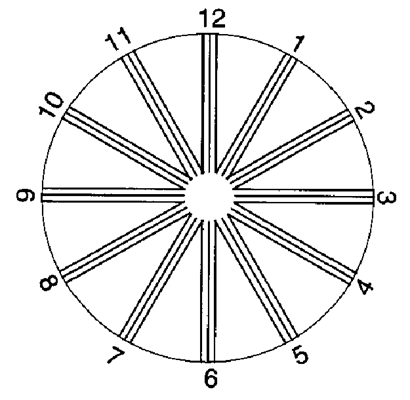

A:判斷自己有沒有散光,最簡單的方法是使用散光表來測試。散光表是一種簡單、方便的方法,但是它的準確度不是特別精確。在配鏡的情況下一般再用裂隙法,或者是交叉圓柱鏡法來精調散光的度數。散光表在網上可以看到,它類似於鐘錶的盤面,有12個數字。各個鏡線……